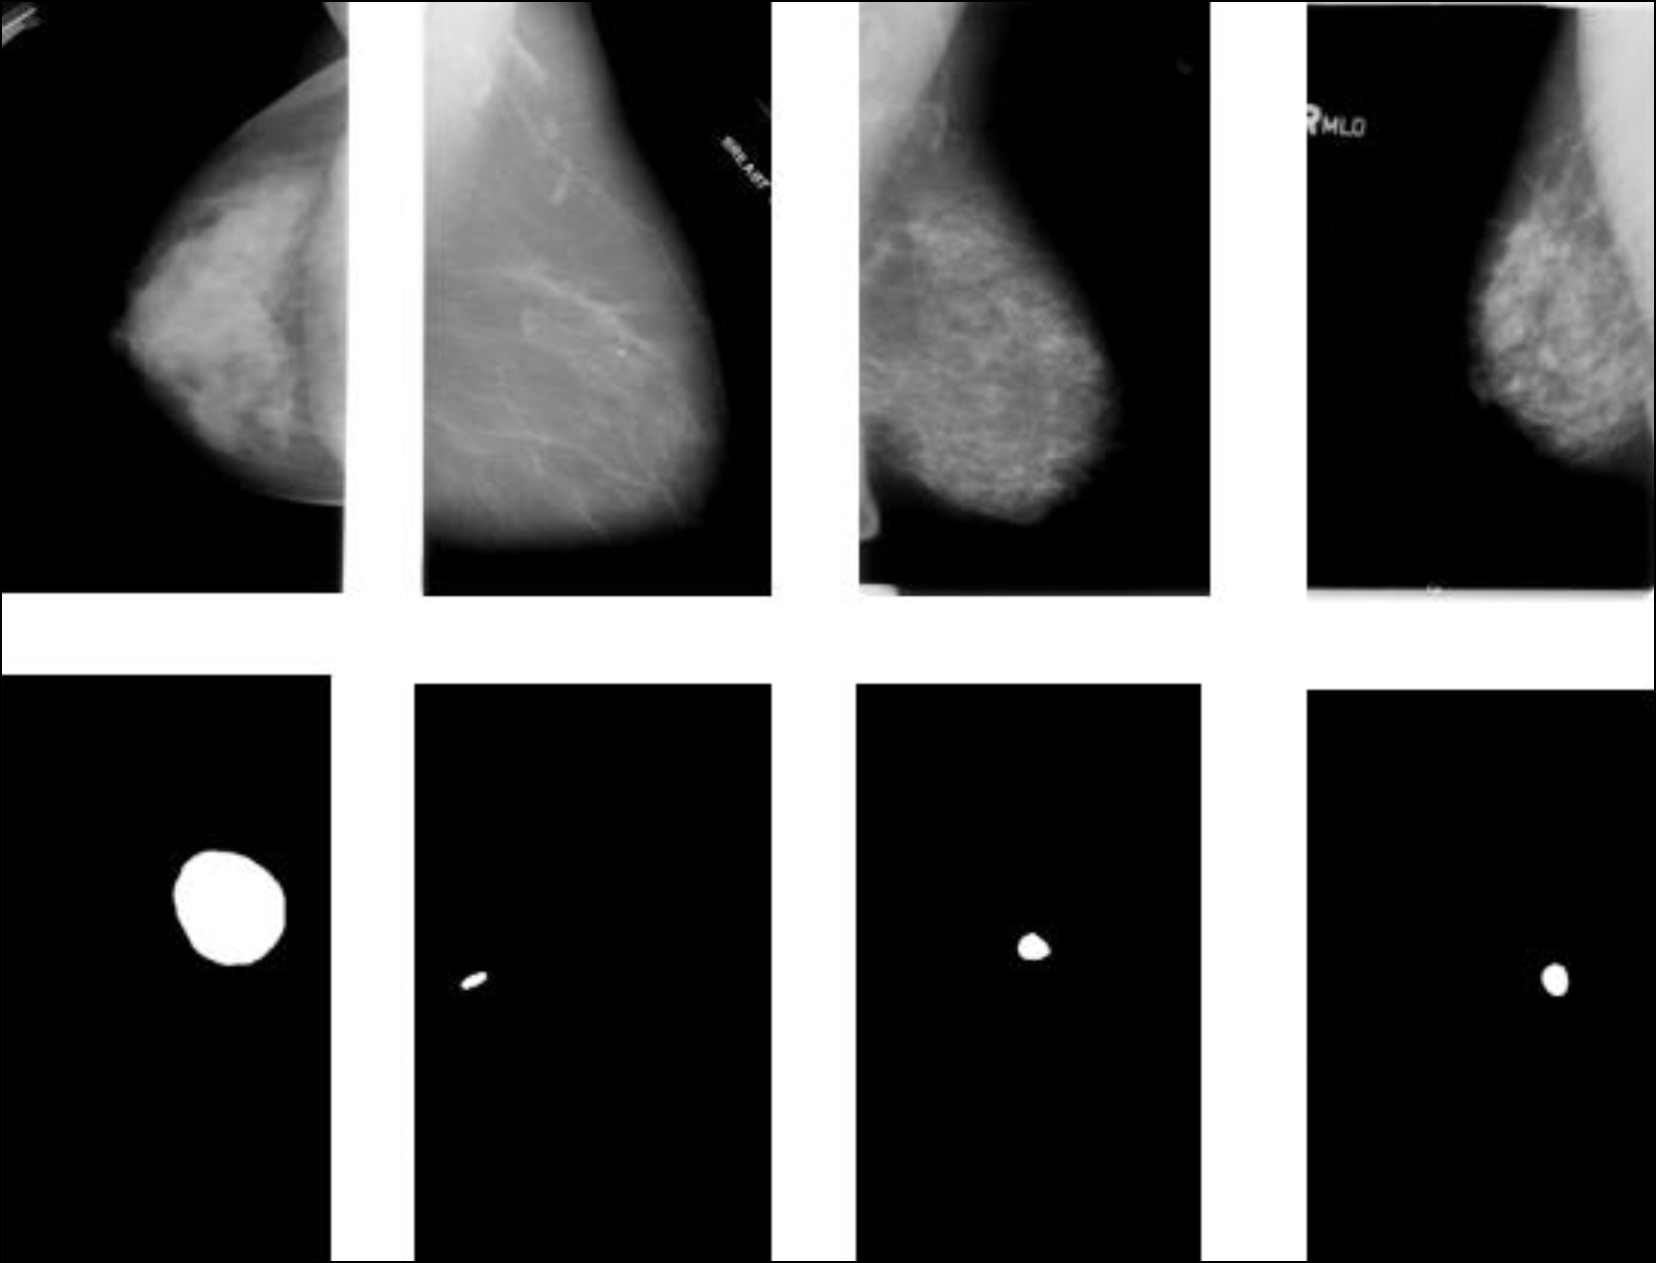

Machine learning techniques for breast cancer diagnosis

Abstract

In the last few years, machine learning techniques have been attracting even greater attention in the field of diagnostics, particularly when detecting breast cancer. Relevant studies dedicated to machine learning techniques in breast cancer diagnosis were analyzed in three areas: solving secondary problems that occur in modern-day breast cancer diagnostics, role in an intelligent assessment of the patient’s condition for preliminary diagnostic decisions, and capability to detect breast cancer risk factors. The results revealed that machine learning techniques applied in breast cancer diagnosis have great potential for improving diagnostic accuracy and efficiency and solving secondary problems. The medical literature analysis has determined the parameters that are used as input data in machine learning techniques. Furthermore, the collected information will be applied to create a parameter system for breast cancer diagnosis using machine learning techniques.

578-591